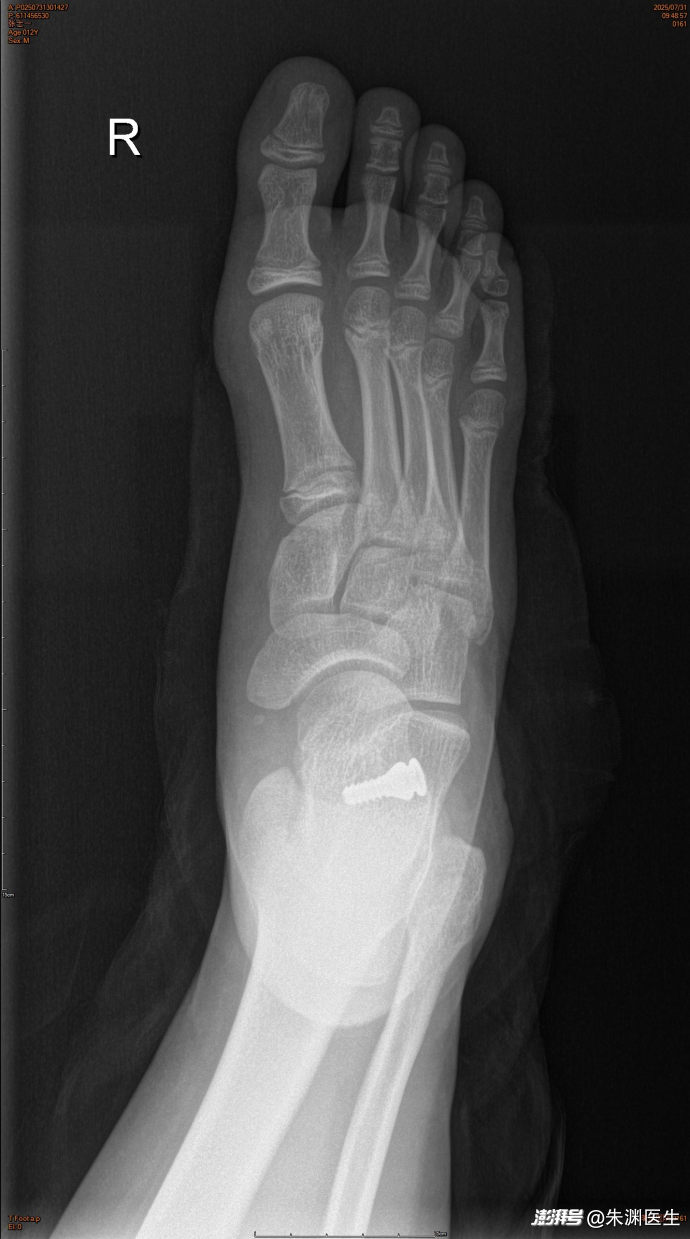

手术治疗青少年平足症。手术前外观、手术后可见骨缝里的金属内植物、术后外观和功能正常。